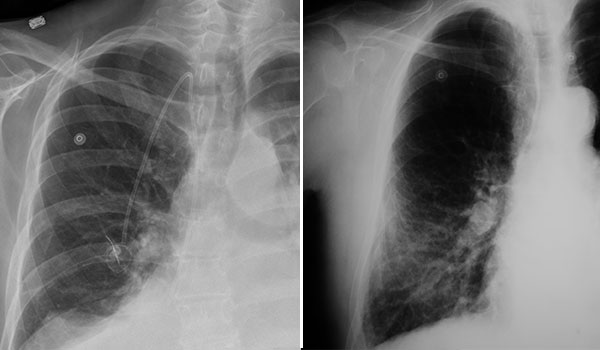

Pleural mesothelioma, which develops in the lining of the lungs, is often mistaken for other more common respiratory conditions like emphysema and pneumonia. People with mesothelioma may initially show shortness of breath, a dry cough or chest pain, making it difficult to distinguish it from other respiratory conditions at first.

Pleural mesothelioma can also cause pleural effusion, which is a buildup of fluid around the lungs, and difficulty breathing. Other chronic lung diseases, infections and lung cancer can all show similar symptoms. These may complicate the diagnostic process and lead to a misdiagnosis of mesothelioma.

Specialists often begin the mesothelioma diagnostic process with imaging tests like X‑rays, CT scans and MRIs to look for fluid buildup or unusual growths. These tests provide important information and help rule out more common conditions, but they can’t confirm mesothelioma.